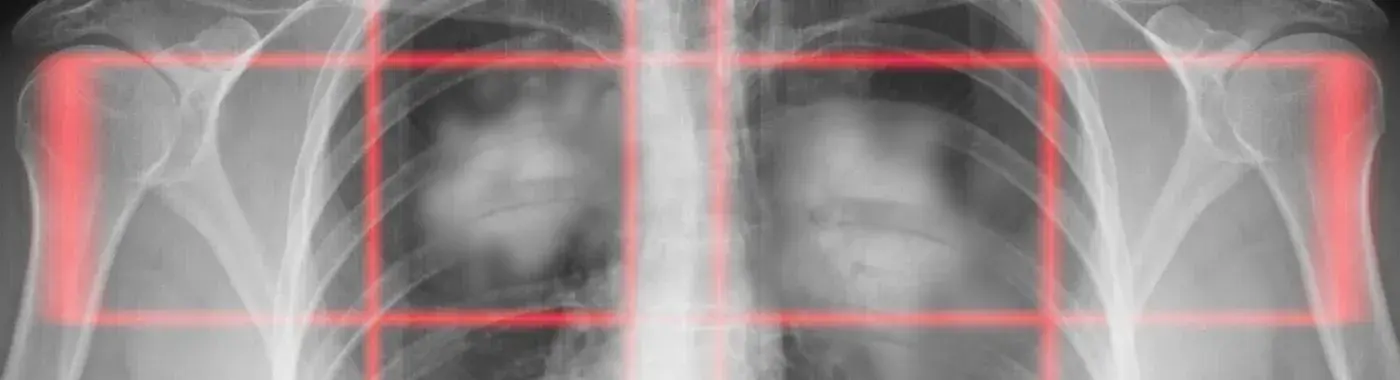

Pancoast Tumor: Understanding a Rare Lung Cancer

A Pancoast tumor is a type of non-small cell lung cancer (NSCLC) that specifically develops in the upper part of the lung, known as the pulmonary apex. These tumors are characterized by their tendency to invade surrounding tissues, including the chest wall, nerves, and blood vessels. Due to their location, Pancoast tumors can lead to a variety of symptoms that may not be immediately recognized as related to lung cancer, making early diagnosis challenging.

• Imaging Studies: Chest X-rays and CT scans are commonly used to visualize the lungs and surrounding structures. MRI scans may also be utilized to assess nerve involvement.